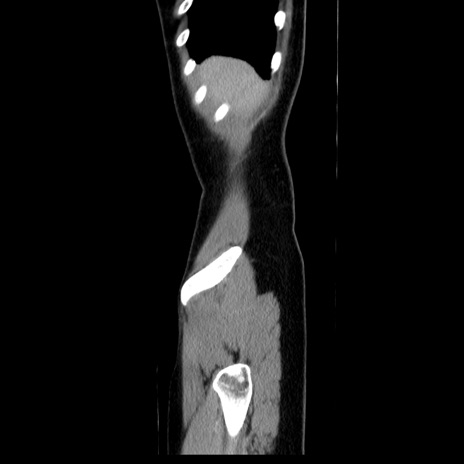

症例39(矢状断像)

【症例】40歳代女性

【主訴】上下腹部痛

【現病歴】2日目から下腹部痛あり。夜間は痛みで眠れなかった。昨日より上腹部痛と下痢が出現。臥位で痛みは軽快したため、休んでいた。本日になって臥位でも立位でも痛みが強くなってきたため救急要請。

【既往歴】子宮内膜症

【身体所見】部:平坦・軟、左上下腹部に圧痛あり、反跳痛あり。

【データ】WBC 21800、CRP 26.78

CT